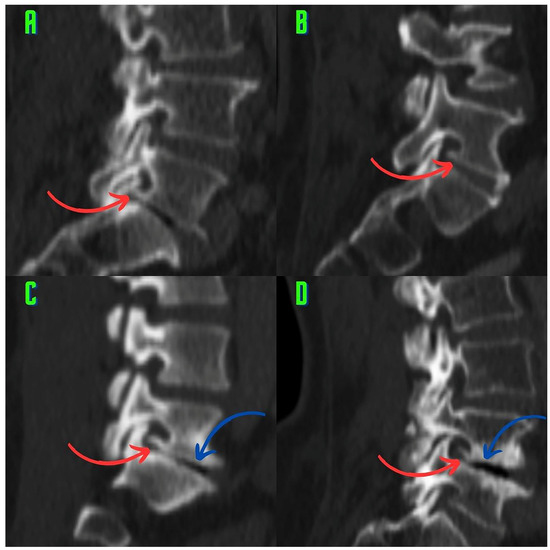

2.3. Image Analysis and Research Methods